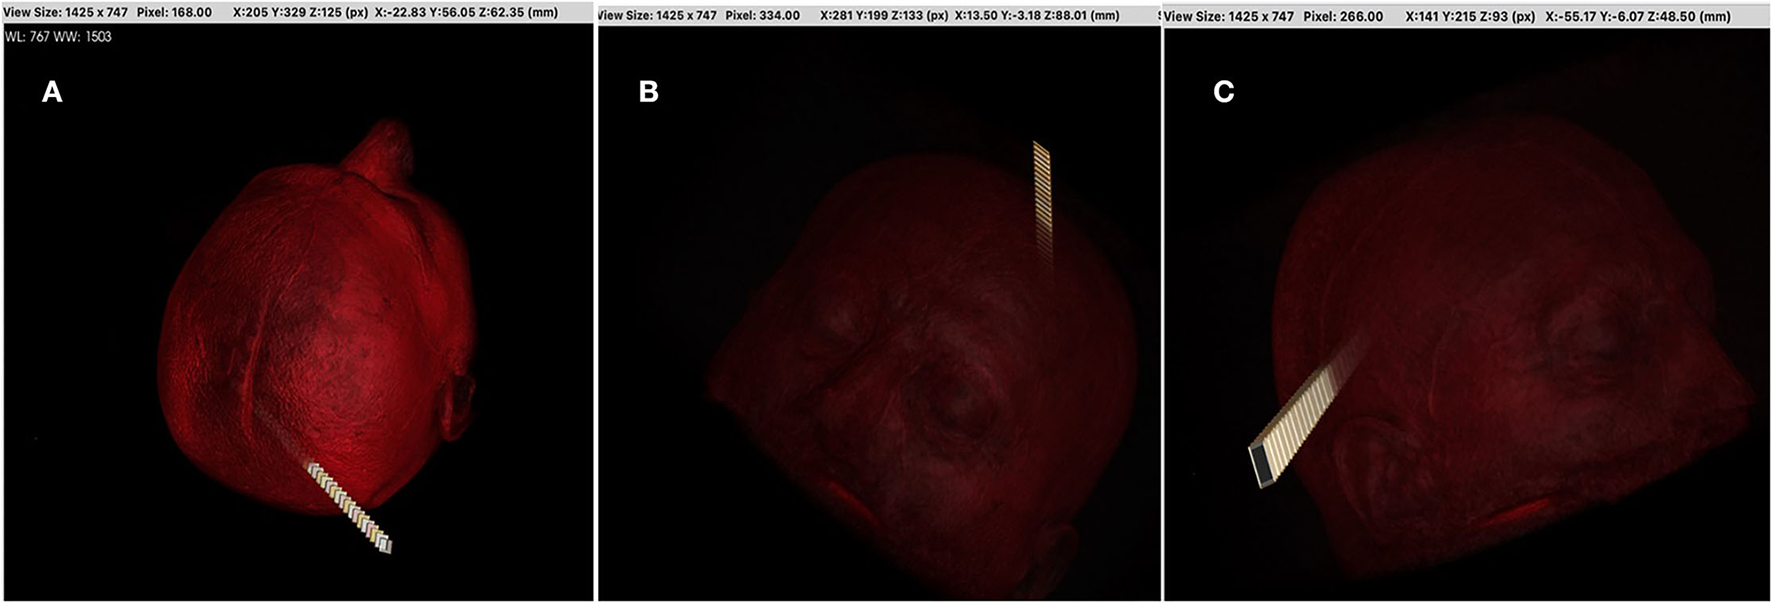

While the total of 40 linear paths extracted from the 16 × 16 and 32 × 32 dimensions was used as reference starting points in Stage 2, the total of 40 linear paths extracted from the 40 × 40 and 64 × 64 dimensions was also used as an environment. Then the extracted nonlinear paths were observed by neurosurgeons. The best path was obtained from the 16 × 16 dimension and are given in Figure 4.

We used (512 × 512 × 144) axial T1-weighted MRI images of one patient with a brain tumor in DICOM format as a case study. We utilized 16 × 16, 32 × 32, 40 × 40, and 64 × 64 path dimensions to evaluate the success of the proposed system architecture. In the first stage, 20 optimal linear paths were extracted for each dimension by using the new heuristic-based algorithm. The optimal nonlinear path was extracted by using the starting points found in the 16 × 16 path dimension. For the 16 × 16 path dimension, the proposed heuristic found 745,984 possible entry points. The areas in Table 2 and the target tumor tissue were accepted as reference points. This algorithm gave input fields of desired diameter and size. These 745,984 linear paths were compared according to the reward and penalty points. By using the intermediate steps, the 20-optimal linear paths were chosen. Then the starting points of these paths were used as reference entry points of the Q-learning algorithm (Figure 4) in the second stage. Then, a matrix size of 78,030 × 78,030 was created and worked on 50 × 25 × 78,030 points for Q-learning. Extracranial areas were excluded. It was enough to find 500,000 epoch paths in a 16 × 16 × 35 environment, and it almost took 70 min. The Q-learning algorithm returns as the best way “node” (Figure 5). Then, the positions of these node values in the matrix were found and the x, y, and z coordinate values were reached. Thus, the coordinates representing the best path were extracted from the DICOM images. The most ideal transcortical tumoral pathway was revealed in Figure 6.

Figure 4. The research algorithm was created for time efficiency compared with the time-consuming RL algorithm. The goal is to find the most ideal cranial entry points. Machine learning was not used in this method. Cranial entry points were scored using the equivalent areas and tumor location in Table 1 and compared with each other. With this algorithm, it was possible to sort by five most ideal entry points, 10 entry points, or worst entry points. In addition, this algorithm provided a linear access path to tumor tissue in the shape of a rectangular prism or cylinder. The entrance area in the images was determined as 1.5 cm2. The algorithm has been adjusted to allow this area to be increased or decreased. This algorithm can be useful in tubular operative systems or rigid endoscopic systems. In this study, we took these points (the most ideal 4,900 points) as the starting points of RL. Image (A,B) are the ideal best rated and image (C) the worst-rated sample entry points.